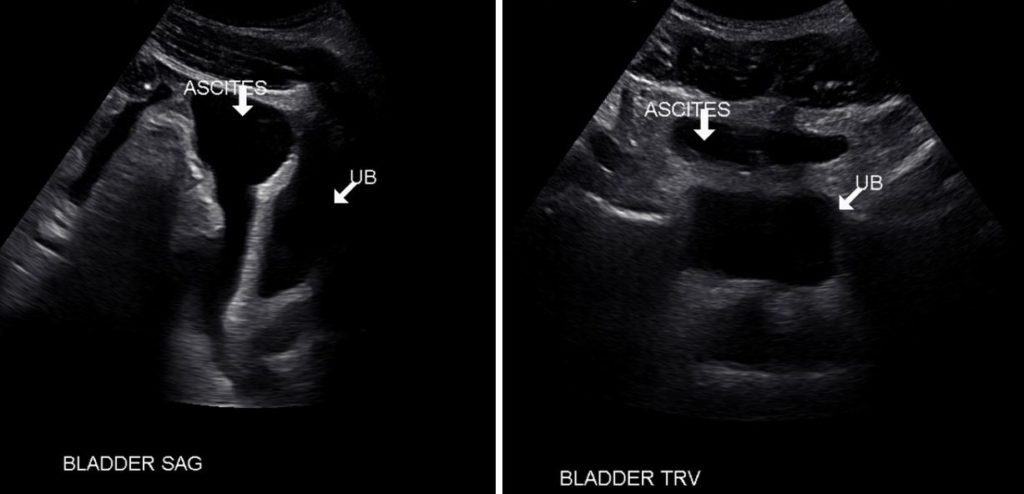

In this patient with ascites, anechoic ascites and bladder filled with urine (UB) can be seen as distinct entities both in longitudinal and transverse planes.